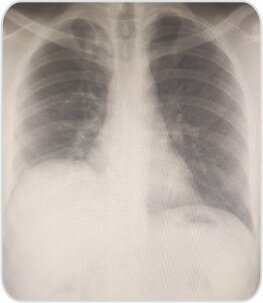

CXR showed right sided pneumothorax. ICD was placed. CT scan showed apical bullae. Uniportal bullectomy was done by Video-assisted thoracoscopic surgery (VATS).

CXR at the time of discharge on POD 3